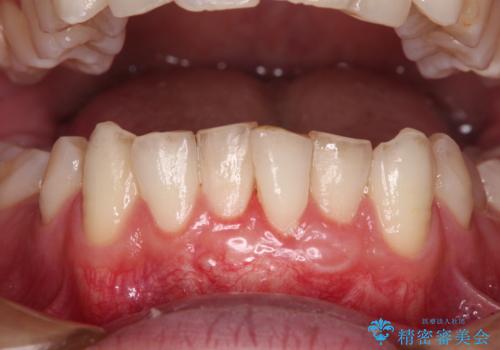

1回目の処置で多少は被覆され歯肉が厚くなりましたが、十分とは言えなかったため、2回目の処置を行いました。

2回目の処置後には十分な厚みと、十分な被覆量を獲得することができました。